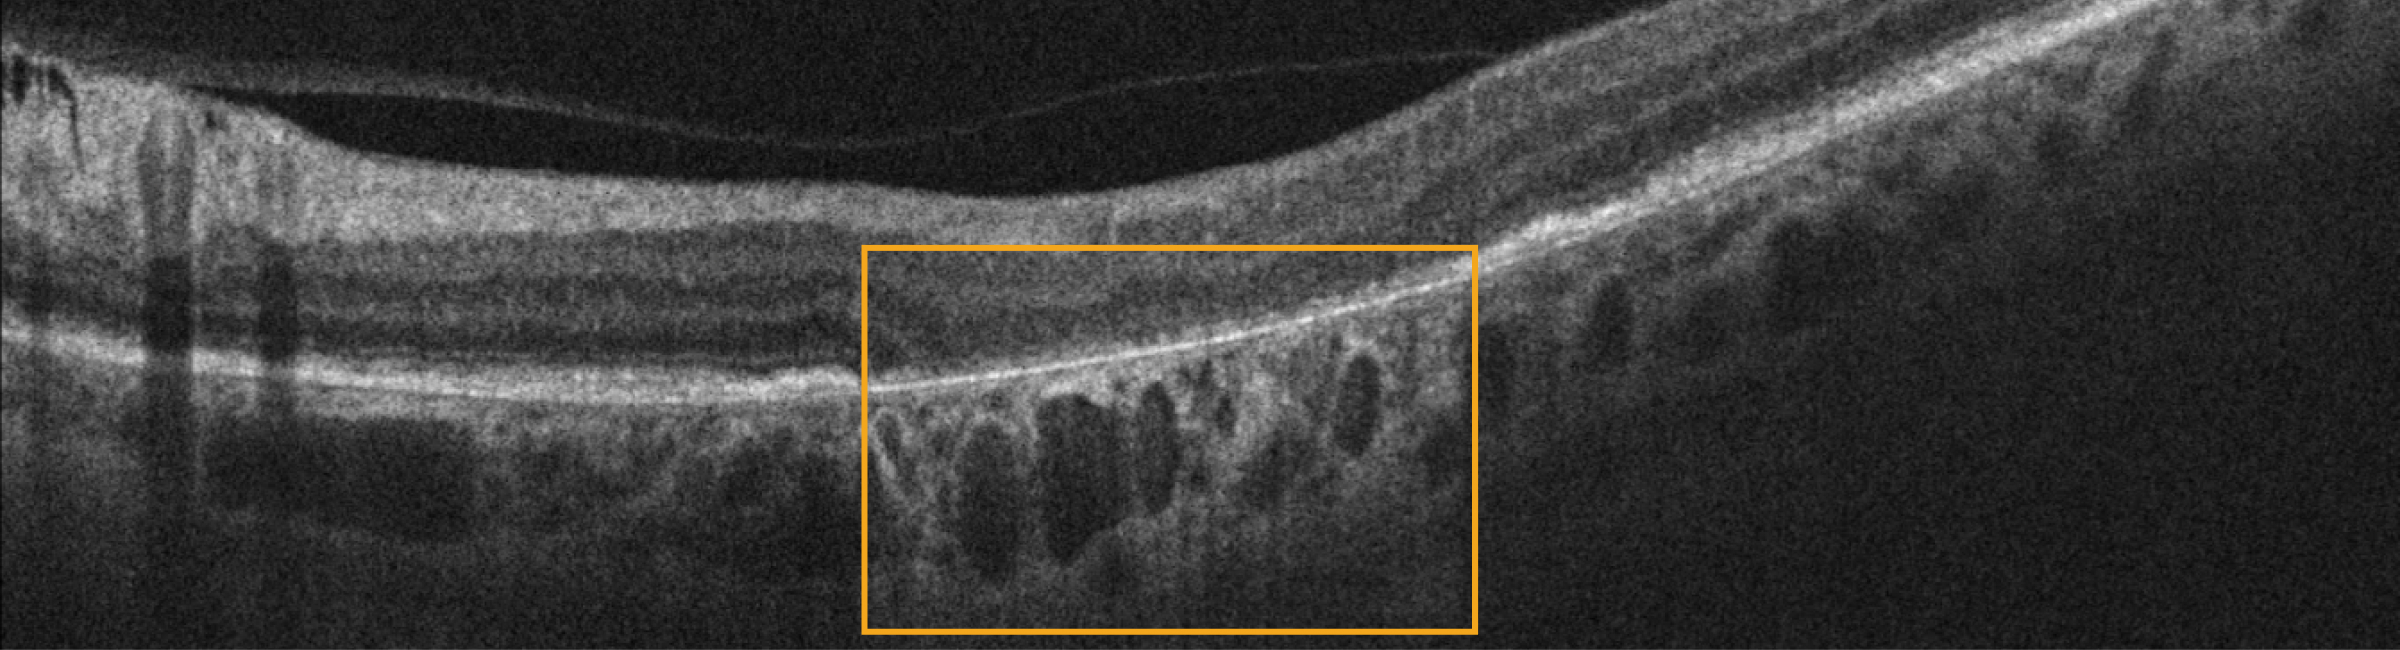

5. Hyporeflective wedges

6. Hyperreflective foci

Well-demarcated, round or dot-like lesions; the number and volume of hyperreflective foci are associated with an increased risk of atrophy.